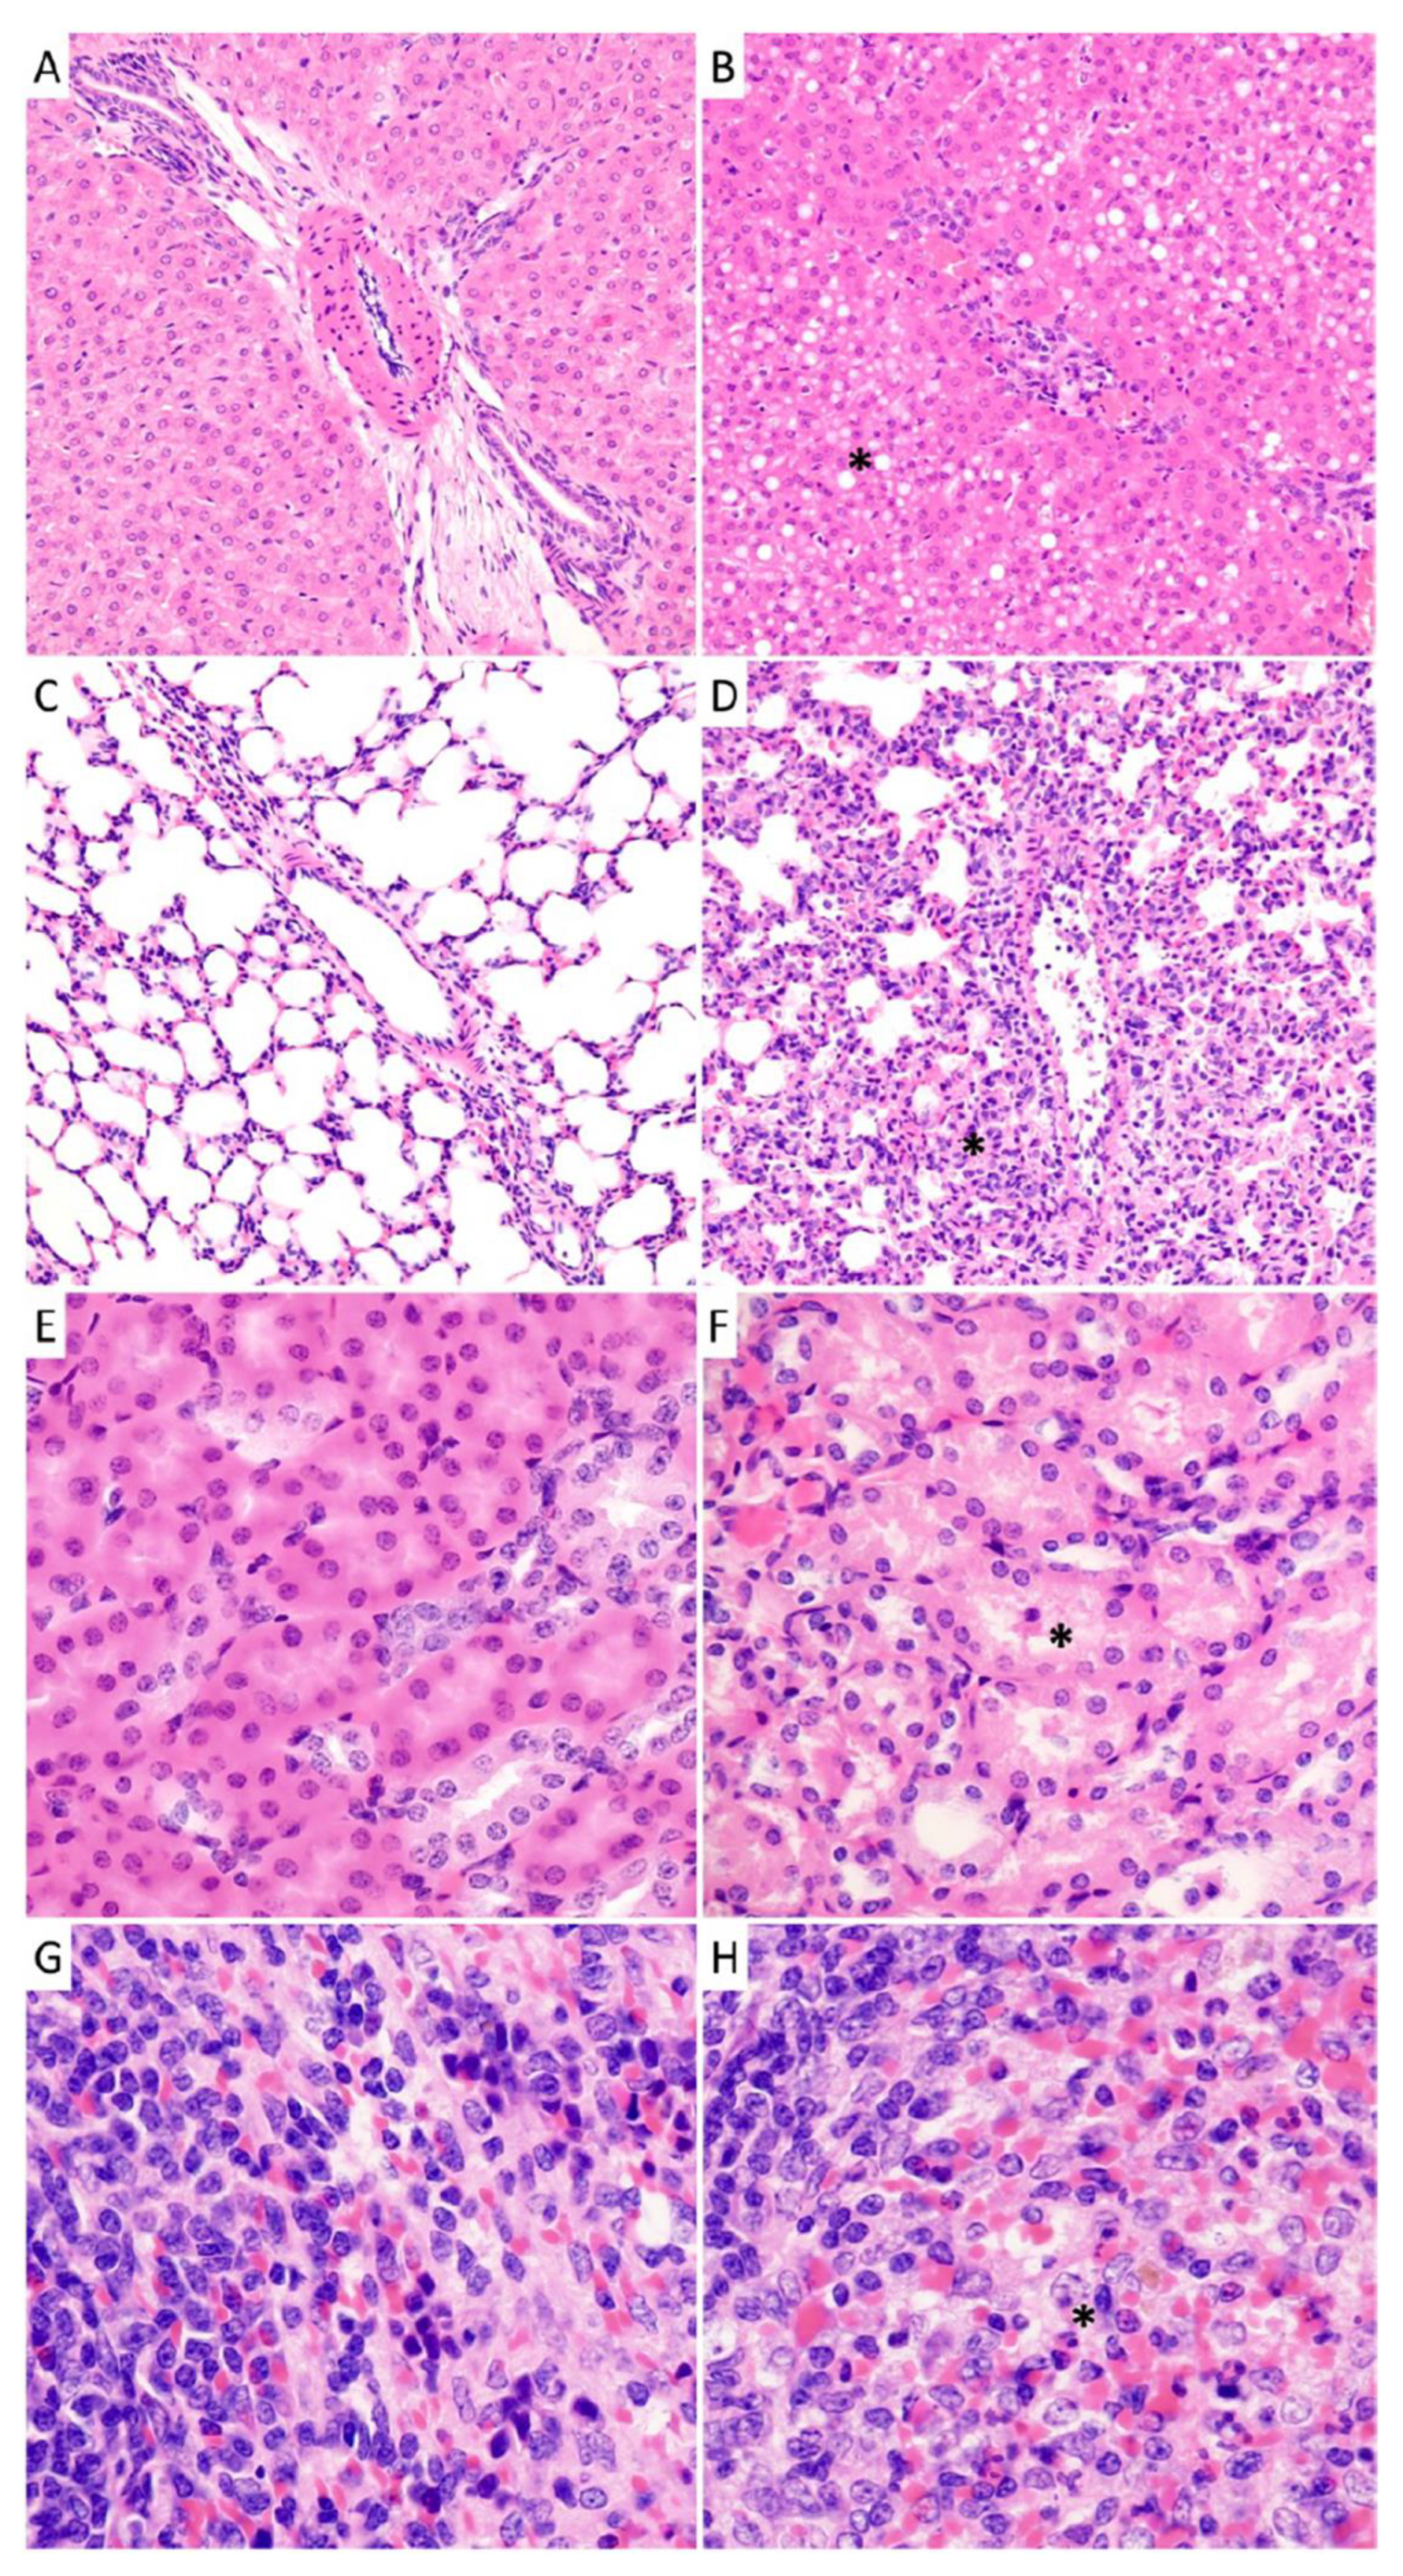

A comprehensive histologic examination was performed on sections obtained from four organs (liver, lung, kidney, and spleen) from each animal. The morphologic features in the liver and lung showed substantial differences and progression in the different animal groups, which correlated with the time of the euthanasia. The most striking findings were the fatty changes in the liver and the interstitial inflammation in the lung, accompanied with the dramatic decrease of open alveolar surfaces in some animals.

Liver specimens collected at days 1 and 3 post-infection were largely unremarkable. Early histopathological abnormalities consisted of minimal necrosis with occasional hepatocellular dropout noted in animals euthanized at day 6. Minimal necrosis remained present in animals sampled at days 9 (two of four guinea pigs) and 12 (three of four) with slight, focal, mostly portal hepatitis observed in two animals examined at day 9 and all animals at day 12 (minimal-to-mild). Signs of steatosis were largely absent in animals euthanized before day 9 post-infection. By day 12 post-infection, three of four animals displayed significant and diffuse steatosis ranging from mild to moderate-to-severe (Figure 8).

Figure 8.

Histopathological analysis of tissues collected guinea pigs infected with NML-61/GPA. Guinea pigs were inoculated with 100LD50 of NML-61/GPA and euthanized at regular intervals for histological analysis of solid organs. Shown are representative liver (A,B), lung (C,D), kidney (E,F), and spleen (G,H) specimens collected early (day 1, (A,C,E,G)) post-infection as well as when animals were moribund (day 12, (B,D,F,H)). Primary observations included significant and diffuse steatosis in liver sections (B) as well as any compromised and damaged alveoli with intra-alveolar fluid in lung sections (D) collected from moribund animals.

Analysis of lung specimens revealed the presence of minimal interstitial pneumonia in each animal across all time points in this study. However, the degree of inflammatory changes showed impressive progression. Minimal or mild-to-moderate changes were noted at days 1 and 3 post-infection, which progressed to severe or moderate-to severe changes in two of four animals examined at the 6- and 9-day time points and four of four animals by day 12. The relatively well-aerated alveoli were better preserved in guinea pigs examined at days 1 and 3, where their estimated average of the four animals was 62.5% and 60% in the examined samples, respectively. This value dropped to 51% of specimens examined from animals euthanized at 6 days and 45% at 9 days. The ratio of the open, well-aerated alveoli dramatically decreased further to an average of 11% in specimens examined from animals euthanized at 12 days post-infection at which point some animals scarcely had spacious, preserved alveoli (5%) without any compromise or damage by compression or intra-alveolar fluid (Figure 8). Pulmonary edema was found in all animals at the 12-day time-point though it was not present in any other groups.

Histological differences were less pronounced in the kidney and the spleen (Figure 8). The histology of the vascular and glomerular units and the renal medulla was unremarkable in all groups. Moderate mononuclear inflammation of the renal sinuses was recorded in animals euthanized on days 9 (subcalyceal in one, subcalyceal and perivenular in one animal) and 12 (subcalyceal in two animals) post-infection. The tubular injury was most significant animals from the 12-day group (mild in two animals, mild with occasional sloughed necrotic tubular epithelial cells in the other two) compared to the animals sampled at day 9 (mild in three animals, minimal in one). The other groups showed mixed findings including unremarkable renal tubules in animal euthanized on days 1 and 3 (one animal per time-point) and two animals sampled at day 6. The other animals in these groups displayed minimal or mild tubular injury. In spleen sections, significant necrosis was not detected across any of the groups. Heterophilic splenitis was displayed in one animal examined on day 6 (minimal), and all four animals euthanized on days 9 and 12 and ranged from minimal to mild. Focal lymphoid depletion was seen in one animal sampled at day 9 and in all four from day 12. Follicular hyperplasia or monomorphic infiltrate at the periphery of lymphoid follicles was observed in one animal at day 3 (minimal), all four animals at day 6 (mild), one animal at day 9 (minimal), and in all four animals at day 12 (mild-to-moderate).